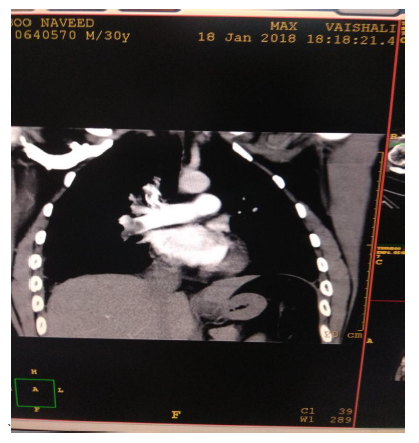

In view of high suspicion of pulmonary embolism in ECHO, CT Pulmonary angiography was done (Figure 3) which showed moderate pulmonary thromboembolism with evidence of hypodense thrombus seen at ramification of bilateral pulmonary arteries (Rt>Lt) extending in segmental branches causing marked occlusion of segmental branches of right lower lobe & lateral segmental branch of left lower lobe & partial occlusion of segmental branches on bilateral upper & lower lobes. A bilateral lower limb Doppler (Figure 4) was done, and no evidence of DVT was found. Treatment with LMWH was initiated. Intravenous thrombolysis was not planned as the patient was hemodynamically stable. A Thrombophilia profile test was sent, which came to be negative. Trop I was 0.06 & NT -proBNP was 426. He responded initially to conservative management, but however, he had persistent high O2 requirement and tachypnea requiring NIV support. He continued to have chest pain on day 5 of ICU admission. His repeat echo was done, which showed dilated RA (Right Atrium) and RV (Right Ventricular) with RVSP 65 mmHg. In view of severe symptoms and right ventricular dysfunction, the patient was planned for catheter-directed thrombolysis. CT Pulmonary Angiography of the Patient showed hypodense thrombus at the ramification of bilateral pulmonary arteries (Rt>Lt) extending in segmental branches of both Right and left lower lobes.

Figure 3 CT Pulmonary Angiography